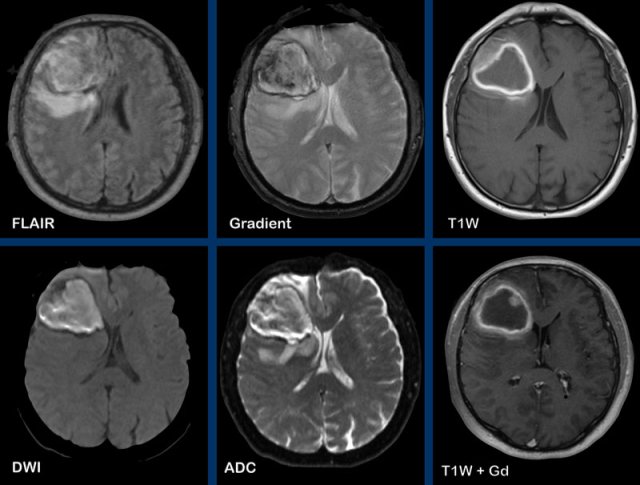

These images are of a 47-year old male, who presented with headache, vomiting and a right-sided hemiparesis.

Images

A ring enhancing lesion is present in the left basal ganglia.

Note the enhancing structures within the inner border of the

enhancement.

There is no diffusion restriction, which makes the diagnosis of an abscess unlikely.

This is a pathologically proven GBM.

These images are of a 55-year old patient, who presented with headache and aphasia.

First look at the images and then continue reading.

- What are the findings?

- What is the most likely diagnosis?

There is a left

frontotemporal lesion, which is bright on T2W, with thick and irregular ring enhancement.

The lesion follows - and extents into the white matter like

the uncinate fasciculus and the u-fibers.

The centre of the lesion shows no diffusion restriction and no enhancement and is most likely necrosis.

The most likely diagnosis is a GMB.